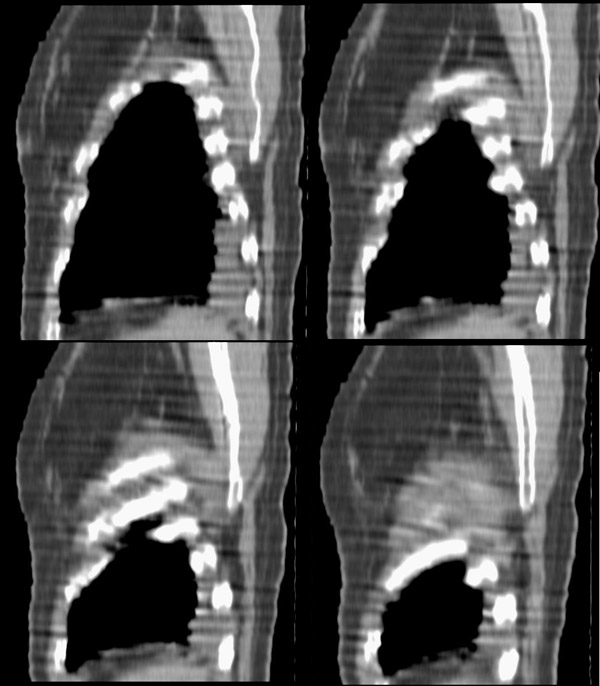

以下是引用形影不离在2008-5-19 21:13:00的发言:[br]左侧胸壁脂肪瘤;肺部还是考虑心衰并肺水肿,胸腔积液。

以下是引用panyishengct在2008-5-19 21:48:00的发言:[br]左侧胸壁脂肪瘤;肺部还是考虑肺水肿,胸腔积液。 [br] [br]左肺门见一团状影,纵隔见淋巴结,建议治疗后复查,以排外中央型肺癌